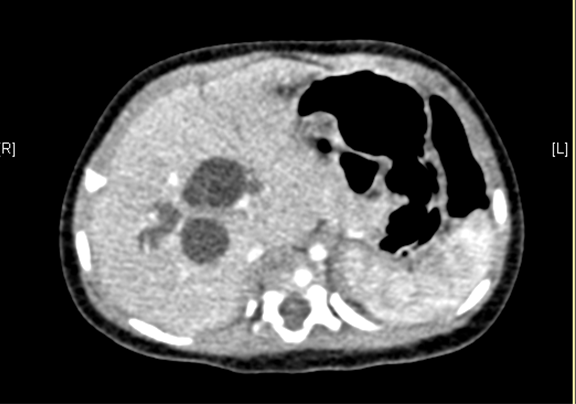

上腹部增强CT:先天性胆管扩张症(胆总管囊肿)可能性大。

术前CT检查:

动脉期

静脉期

平衡期